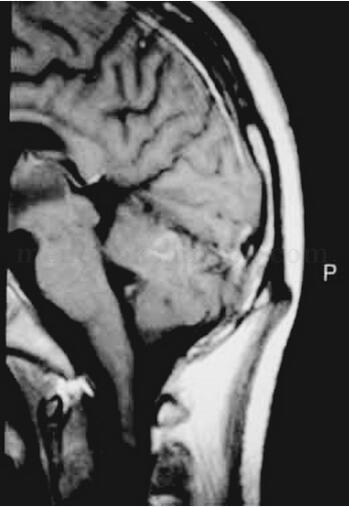

1小时条评论女,40岁。 主诉:肢体运动障碍2个月,不能说话10天。 病史:患者于2月前晨起突发左侧上肢活动不灵、麻木、说话吐字不清,在当地中医学院附属医院就诊,头颅MRI:双侧脑室旁及半卵圆中心小片状长T2信号,按脑梗死给予低分子右旋糖苷、川芎等药物治疗,病情进行性加...